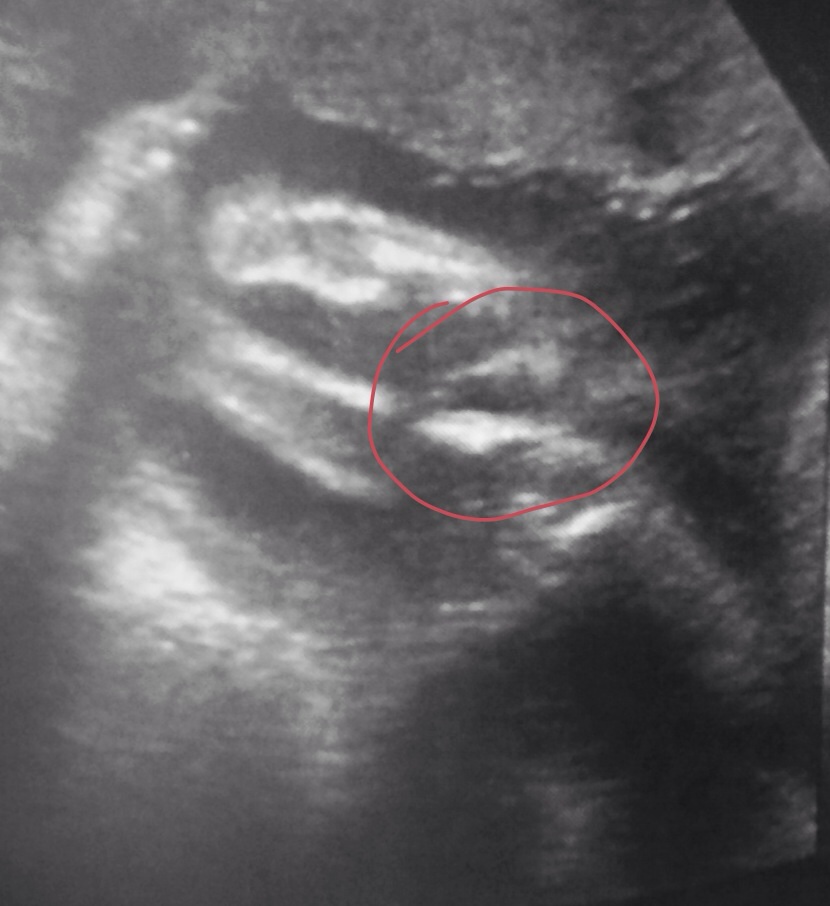

26 weeks scan

Can't really make anything out in that area. Do you have any others?

Any guesses with skull.

Maybe boy on your potty shot. What did the tech say?

That must be frustrating. That could also be a cord though... Do you have any 12-14 week side shots/nub pics?